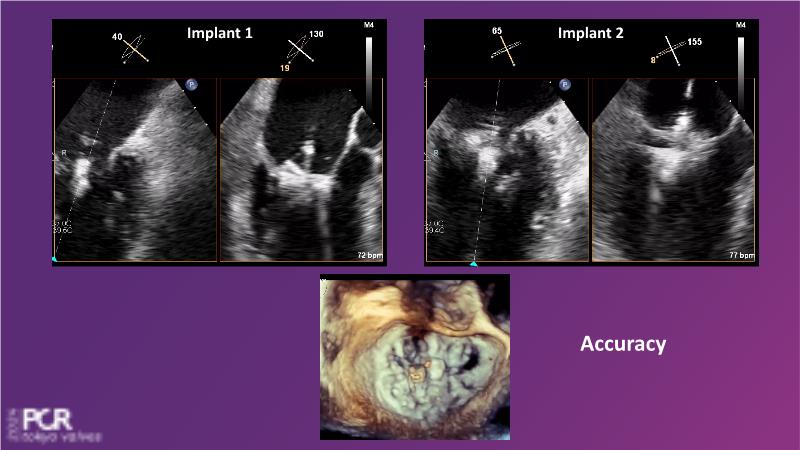

Watch this session to get an overview of a new TEER device, follow the step-by-step procedure related to initial experiences with this device for a Japanese patient with degenerative mitral regurgitation, learn about the latest data from RCT and registries, and follow discussions of challenging TEER cases!

- To understand how novel TEER device provides new possibilities in TEER

- To learn procedural step-by-step of novel device